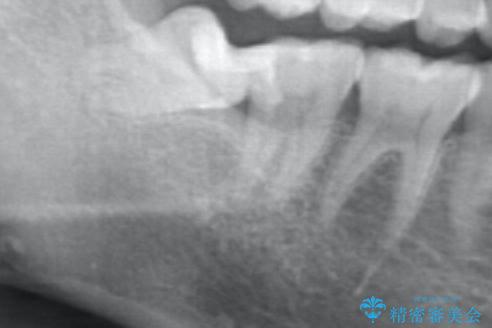

デンタルX線写真より失活・根尖性歯周炎の問題が認められるので、根管治療・ファイバーコア築盛・オールセラミッククラウンの治療を行います。

X線写真で根尖に黒い透過像が見られる場合は、きちんと根管内を無菌的な状態にしてからファイバーコアを築盛して根管系を封鎖した後に審美性の回復をクラウンにて行うことが肝要です。

根管治療は根尖部の透過像が縮小し根尖性歯周炎の治癒の傾向がX線写真から、ジルコニアクラウンはクラウンと歯ぐきの調和が写真より見て取れます。